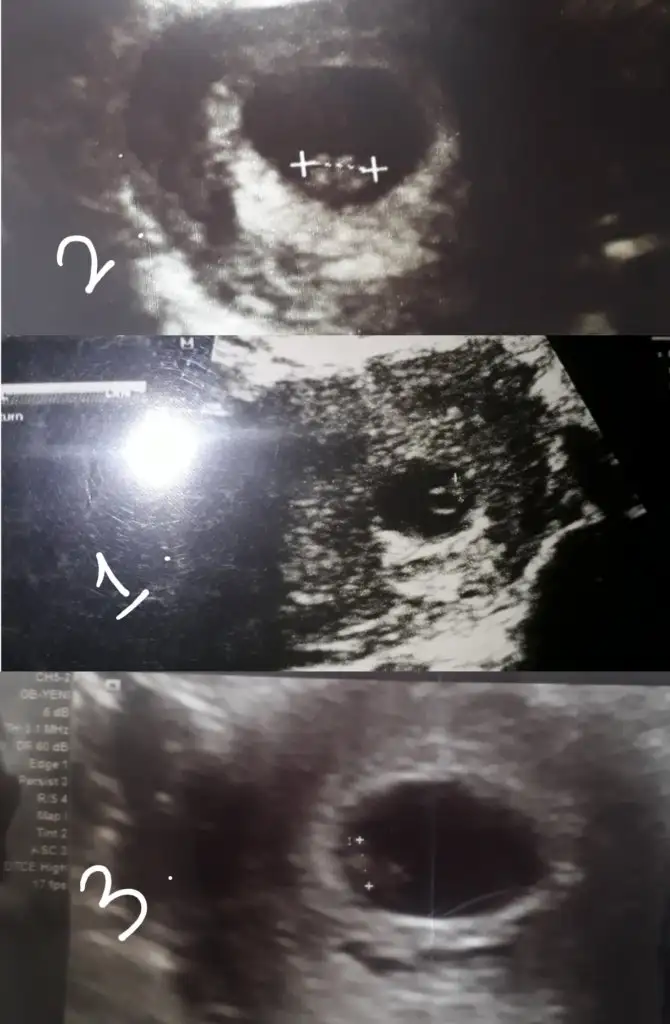

Merhaba canım benim lekelenmem adetten üç gün sonra başladı hala da devam ediyor. Kahverengi olduğu için ve kanama şeklinde olmadığı için iki Farklı doktora gitmeme rağmen olabilir dediler. Ki gittiğim doktorlardan biri bir Prof. perinatolog. Bana dinlen ağır iş yapma ama günlük hayatına devam edebilirsin eğer bu sağlıklı bir gebelikse kalır değilse düşer dediler. Kese yeni daha 6 mm kalp atışını henüz duymadık.

6 mm mi kuzum kesen ne kadar

Kızlar ultrason sonuçlarınızı rica etsem atabilir misiniz doktor üstten bakınca 5mm demişti alttan usg görüntüsünde 2,52 mm yazıyor Yolk kesesini gördüm dedi örnek görüntülere baktım hiç bnmkine benzemiyor